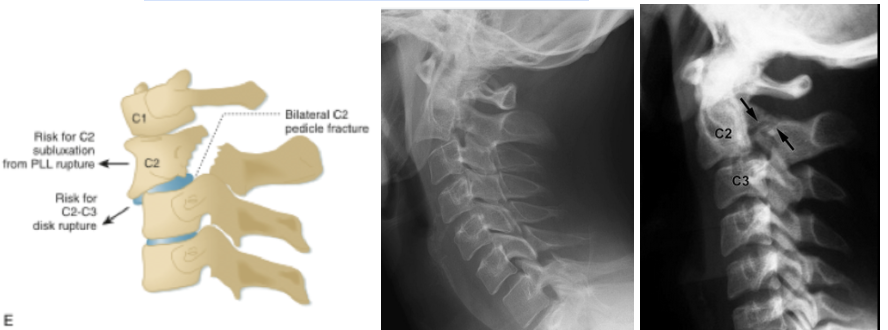

H - Hangman’s fracture (C2 pedicular fracture)

1. Forceful hyperextension of the head with neck distraction resulting in bilateral C2 pedicular fracture with/without anterior translation of C2 on C3

2. Also known as traumatic spondylolisthesis of the axis, but the term “hangman’s fracture” is misleading since this injury is more likely to result from MVC or fall

3. Three types classified by degree of translation and angulation, but Type 1 is stable and Type 2 and 3 are unstable

4. Often not an isolated fracture and up to 30% of patients have an additional cervical spine injury to contiguous or noncontiguous levels

5. Spinal cord injuries are rare since the diameter of the spinal canal is the largest at C2 and the subluxation widens it further